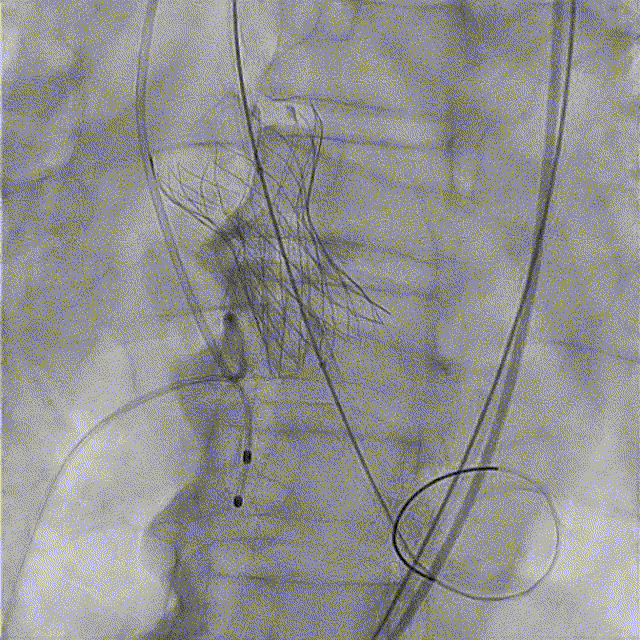

全麻后超声引导下建立入路,左侧股动脉置入TaurusNavi 20F血管鞘。跨瓣后左室放置Lunderquist导丝,使用TaurusAtlas 20mm球囊预扩,球囊无明显位移,有轻微腰征、无漏。输送系统预备同侧Snare从右股动脉送入,安全顺利通过主动脉弓。瓣膜在双窦展开位约瓣上2mm位初始定位释放,工作位造影多角度评估后予以释放(一次定位释放,未采用多次回收功能)。超声下显示瓣膜偏椭圆,之后使用TaurusAtlas 22mm球囊后扩,支架形态改善明显,导管测压由术前的70mmHg即刻下降至1mmHg,术后即刻超声心动图评估显示瓣膜位置良好,微量瓣周漏,血流动力学指标理想。

完全释放

球囊后扩